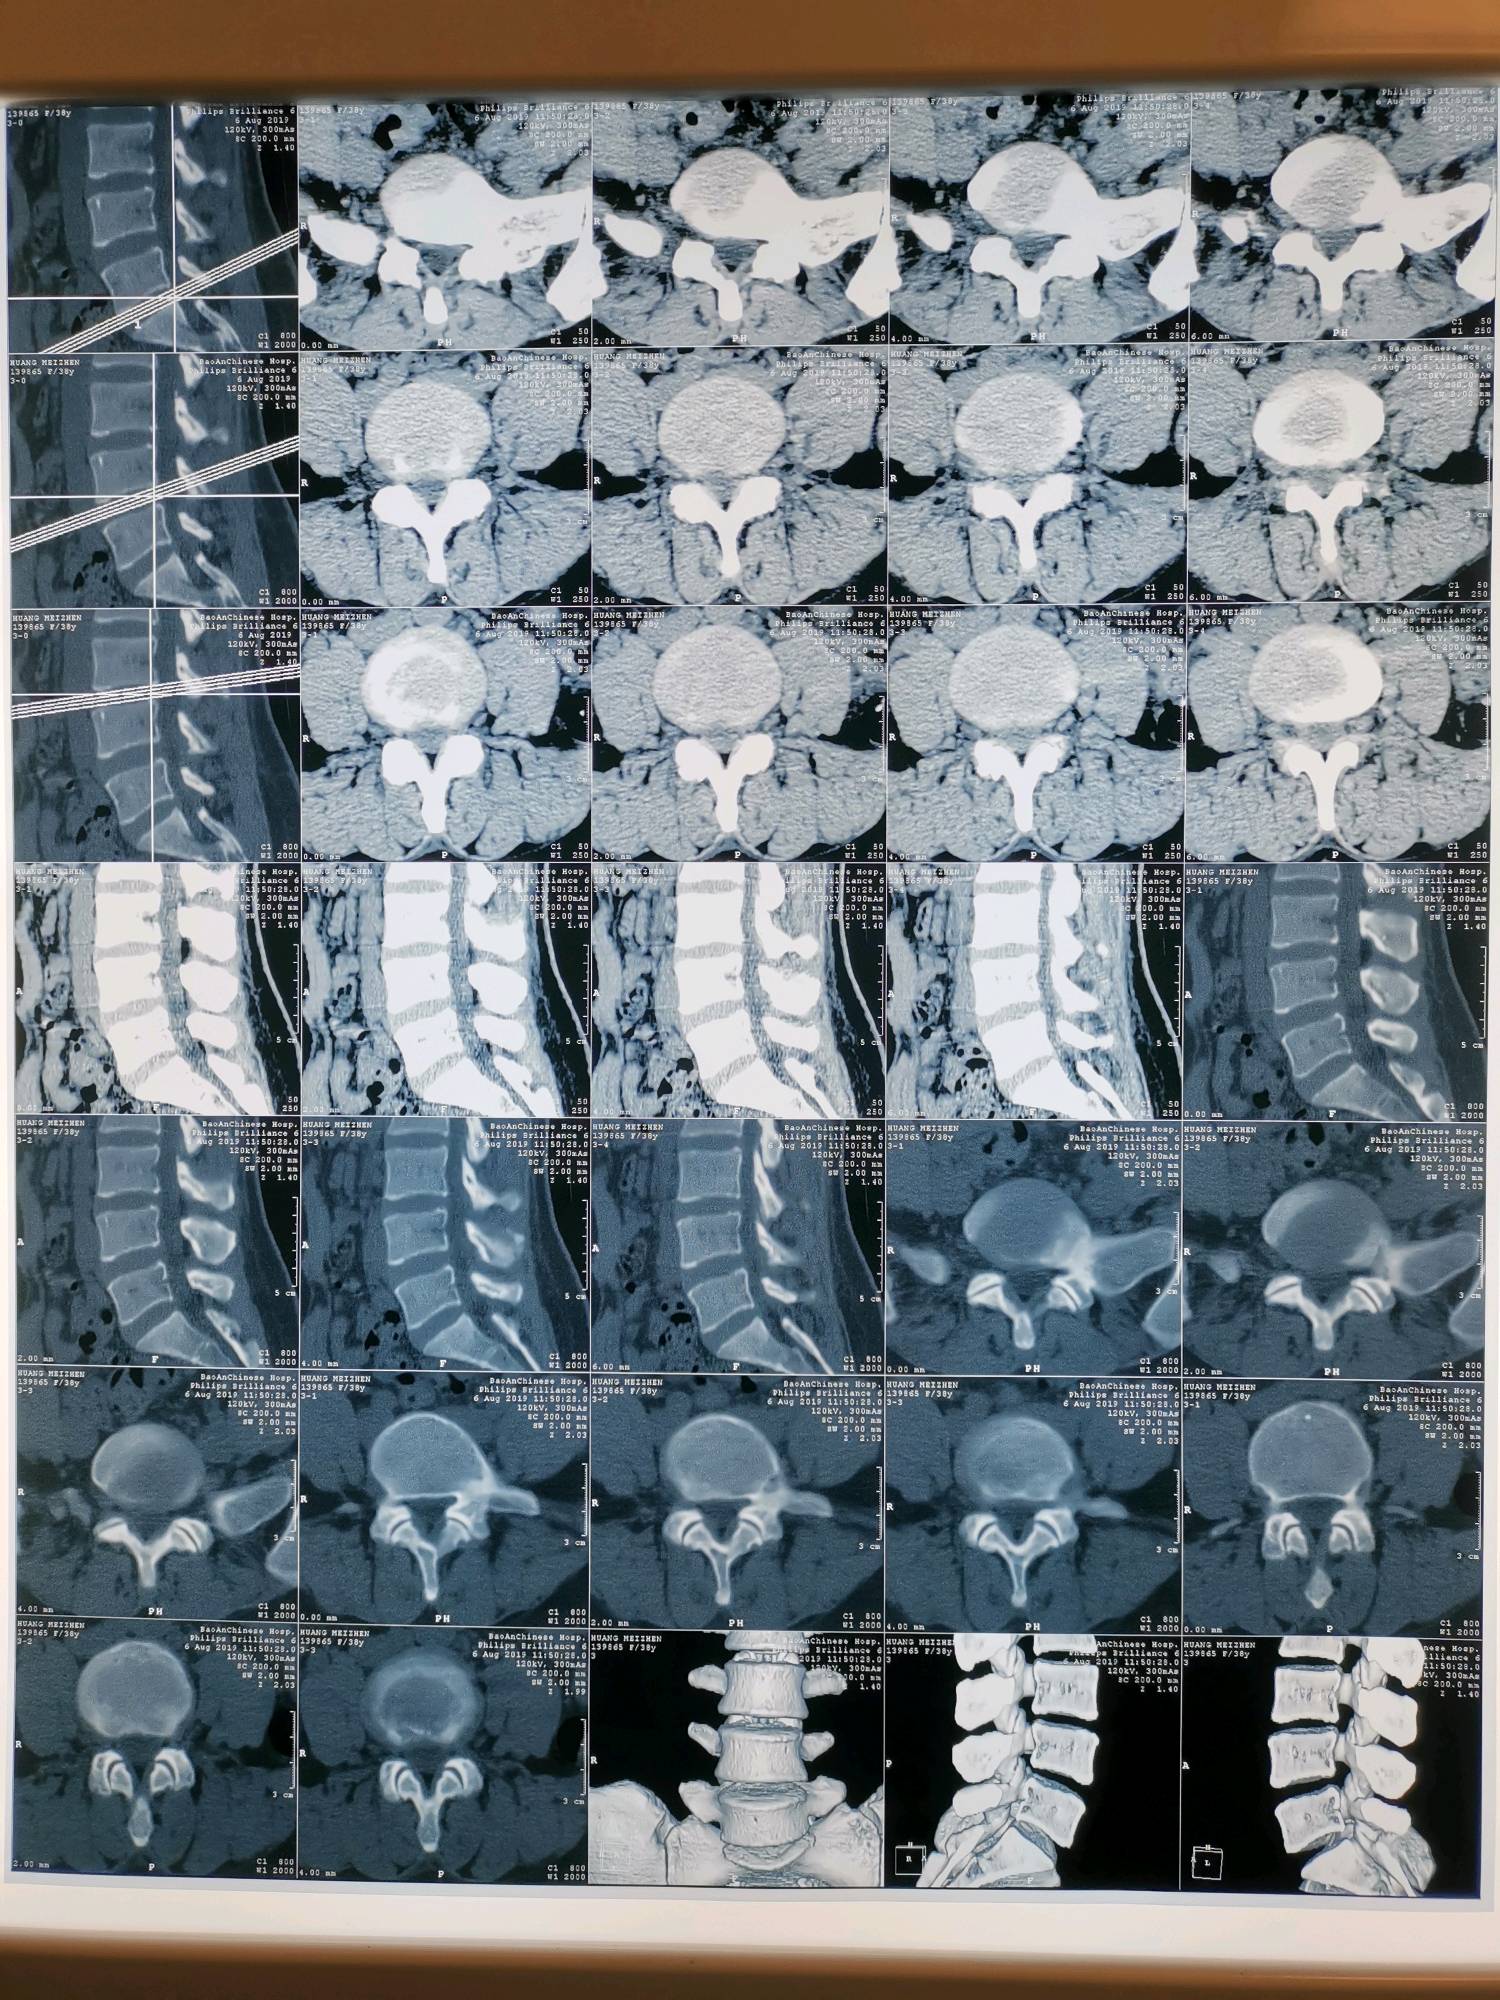

影像:自带腰椎CT未见异常。拍站立位骨盆平片示:双侧髂骨翼不对称,耻骨联合不等高。

齐伟主任指出:患者在正规三甲医院按腰椎间盘突出症治疗一个月无效,首先置疑“诊断”的正确性。自带腰椎CT片未见明显间盘突出和神经根受压,更加怀疑“诊断”的可靠性。查体时患者腰部无明显压痛及放射性疼痛,直腿抬高时无下肢放射性疼痛,无皮肤感觉障碍,跟膝腱反射正常,故否定“腰椎间盘突出症”的诊断。“右侧直腿抬高30度时臀部剧痛、下肢无疼痛”为直腿抬高试验假阳性,并非直腿抬高30度,是骶髂关节及臀部肌肉疼痛限制的结果,屈膝屈髋试验可以证实,真阳性为腰及下肢的牵扯性疼痛。右侧臀大肌、臀中肌僵硬,压痛(+),向小腿外侧放射,右侧直腿抬高及屈膝屈髋时臀部剧痛,无下肢放射性疼痛,右足外旋多于左侧,右侧“4”字试验(+),拟诊断为“骶髂关节错缝、臀大肌损伤、臀中肌损伤”。针刀正骨治疗一次后症状明显减轻,验证了“拟诊断”的可靠性,方向正确,效不更方,故能三次而愈。